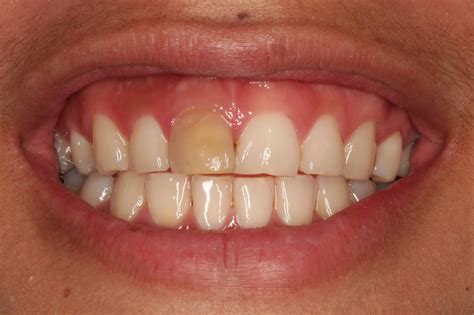

• Darkening or discoloration of the tooth.

The pulp inside your tooth is vital during its development, but once a tooth is fully mature, it can survive without the pulp if the surrounding tissues remain healthy. An Rct of teeth is indicated when the pulp becomes inflamed or infected due to deep decay, repeated dental procedures on the same tooth, or traumatic injuries. If left untreated, the infection can spread, leading to abscesses, bone loss, and severe pain.